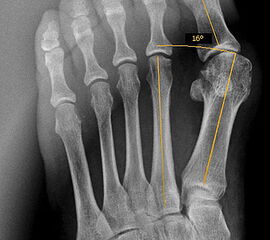

Operationsplanung anhand der Röntgenaufnahmen unter Beachtung wichtiger radiologischer Landmarks wie Intermetatarsalwinkel, Hallux valgus – Winkel, Distaler Gelenkflächenwinkel (Distal metatarsal articular angulation: DMAA), Metatarsaleindex und Sesambeinposition (Abbildung 1)

816. Der Apex des 60° Winkels soll, wie von Austin beschrieben, im Zentrum des ersten Metatarsaleköpfchens (MTK 1) liegen. Liegt der Apex weiter distal, resultiert eine erhöhte Frakturgefahr für das Köpfchen. Weiter proximal verringert sich die spongiöse Kontaktfläche der Osteotomie. Die Sägeebene kann alternativ auch durch einen Kirschnerdraht im Apex der Osteotomie, der bei längenneutraler Ausrichtung senkrecht auf die Achse des zweiten Metatarsale zielt, markiert werden."> 816. Der Apex des 60° Winkels soll, wie von Austin beschrieben, im Zentrum des ersten Metatarsaleköpfchens (MTK 1) liegen. Liegt der Apex weiter distal, resultiert eine erhöhte Frakturgefahr für das Köpfchen. Weiter proximal verringert sich die spongiöse Kontaktfläche der Osteotomie. Die Sägeebene kann alternativ auch durch einen Kirschnerdraht im Apex der Osteotomie, der bei längenneutraler Ausrichtung senkrecht auf die Achse des zweiten Metatarsale zielt, markiert werden." srcset="/assets/images/h/9-ampjy24ne22jbef.jpg 1x, /assets/images/5/9-130tkqcqkn7t759.jpg 1.5x, /assets/images/z/9-5w1jfh92tmfvfgh.jpg 2x" width="270" height="240" loading="lazy">

Die Chevron Osteotomie ist eine der weltweit am häufigsten angewandten Verfahren zur Korrektur einer milden bis mittelgradigen Valgusfehlstellung der Großzehe 1110121319148. Die zahlreichen Publikationen berichten über relativ verlässlich gute und reproduzierbare Ergebnisse. Durch Modifikationen in der Operationstechnik versuchten einige Autoren den Indikationsbereich auf mittelgradige bis schwerwiegende Fehlstellungen auszuweiten 121314. Die Bestimmung des Schweregrades der Fehlstellung erfolgt in erster Linie am belasteten Röntgenbild im dorsoplantaren Stahlengang (siehe Abbildung 1). An dieser Aufnahme können die wichtigsten radiologischen Vermessungen zur Operationsplanung vollzogen werden 112310121312728172930, auch wenn in einigen Studien eine große inter- und intraindividuelle Schwankungsbreite der Messergebisse dargestellt werden konnte 2930. Ebenso zeigt sich eine gewisse Varianz in der Methodik zur Bestimmung des ersten Intermetatarsalwinkels 18282931. Als Grenzwerte für einen milden bis mittelgradigen Hallux valgus werden in der Literatur in relativ weiter Übereinstimmung ein Intermetatarsalwinkel bis maximal 16° und ein Hallux valgus Winkel bis 40° genannt 688. Der DMAA ist radiologisch schwierig zu beurteilen und sollte intraoperativ bei Gelenkeröffnung inspektorisch überprüft werden 2. 2007 verglichen Trnka et al. (2007) die Ergebnisse von vier verschiedenen Nachuntersuchungsgruppen, die sich durch Modifikationen der OP Technik unterschieden: 66 Chevron Operationen von 1991 bis 1992, 100 Chevron Operationen von 1992 bis 1995, 55 Chevron Operationen von 1994 bis 1995 und 89 Chevron Operationen von 2000 bis 2002. So wurde der dorsomediale Zugang 1992 durch einen streng medialen Zugang mit L-förmiger Kapsulotomie ersetzt. 1992 wurde das laterale Release über einen dorsalen Zugang eingeführt mit Perforation der lateralen Kapsel längs zwischen Metatarsale 1 und fibularem Sesambein, sowie vertikal im Verlauf der Gelenklinie ohne Ablösung des Adduktors oder Durchtrennung des intermetatarsalen Bandes. Zwischen 1994 und 2000 wurde eine temporäre Fixation mit einem Kirschnerdraht durchgeführt. Seit 2000 wird die Osteotomie mit einer kanülierten Kompressionsschraube fixiert. Insbesondere die Einführung des lateralen Release führte zu einer signifikanten Verbesserung des Hallux valgus- und Intermetatarsalwinkels, ohne vermehrt Probleme mit einer avaskulären Nekrose des MTK 1 zu bekommen. Die Einführung einer Osteosynthese mittels Kirschnerdraht zeigte im follow up nach 34 Monaten gegenüber der lediglich manuellen Einstauchung des distalen Fragments, wie in der Originalarbeit von Austin beschrieben, eine geringere Rate an Korrekturverlusten und Dislokationen des ersten Metatarsaleköpfchens. Durch die Verwendung einer Schraube konnte das Indikationsspektrum hinsichtlich Schweregrad des Hallux valgus erweitert werden. Der Vergleich einer 2-Jahres- und eines 5-Jahres-Nachuntersuchung zeigte gegenüber der präoperativen Untersuchung eine Verbesserung des IM-Winkels von 13° auf 8° respektive 9°. Der HV-Winkel konnte von durchschnittlich 29° auf 15° respektive 16° reduziert werden. Ergebnisse, welche auch die langfristige Zuverlässigkeit der Chevron-Osteotomie in der Behandlung des milden bis mittelgradigen Hallux valgus belegen.